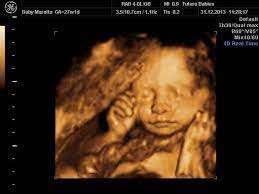

When Is It The Best Time To Do A 3d 4d Ultrasound December 2018 Babies Forums What To Expect

When Is It The Best Time To Do A 3d 4d Ultrasound December 2018 Babies Forums What To Expect from images.agoramedia.com